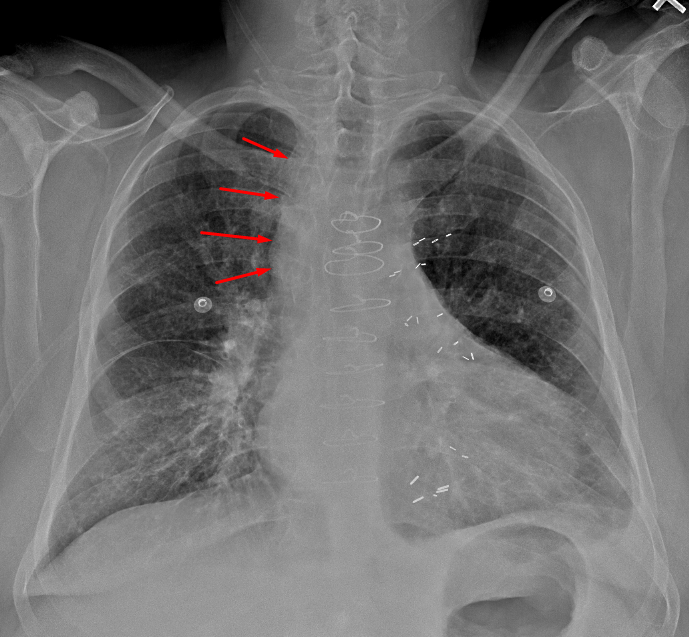

Age: 66

Sex: Male

Indication: Chest pain

Sample ReportWidening of the right paratracheal stripe, which raises concern for lymphadenopathy. Recommend chest CT for further evaluation.

Mild interstitial pulmonary edema with small bilateral pleural effusions.